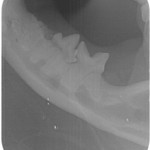

Tænder med TR skal trækkes ud. Men alligvel er det nødvendigt at tage tandrøntgen af alle tænderne for at se om der er andre tænder, der er angrebet af TR.

På Dyretandspecialist kan du læse mere om sygdommen Tooth Resorption (TR/FORL) hos katte. Her kan du både se røntgenbilleder og billeder af tandsygdommens stadier, samt se symptomerne på sygdommen, så du ved, hvad du skal være opmærksom på hos din kat.

Nedenfor kan du se de 8 røntgenbilleder af Shana-Mio´s tænder, som specialtanddyrlægen tog af hendes tænder i 2008, da hun fik konstateret TR/FORL: